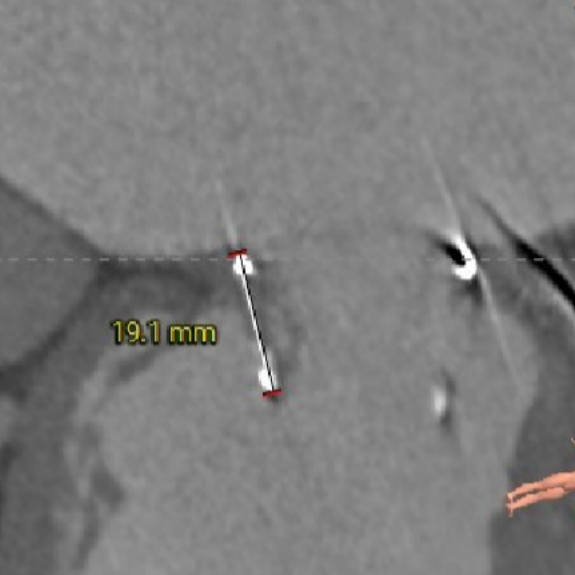

二尖瓣瓣架高度

选瓣依据:该二尖瓣原置换生物瓣为Hancoke II#31 ,CT测量生物瓣瓣环周长折算直径约28.0mm,瓣架高度约19.1mm;